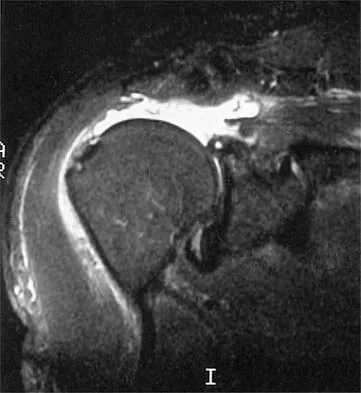

An 80-year-old man has had increasing shoulder pain for the past 4 months. He reports that it began with soreness and stiffness after chopping some wood. A coronal MRI scan is shown in Figure 16. Initial management should consist of

Explanation